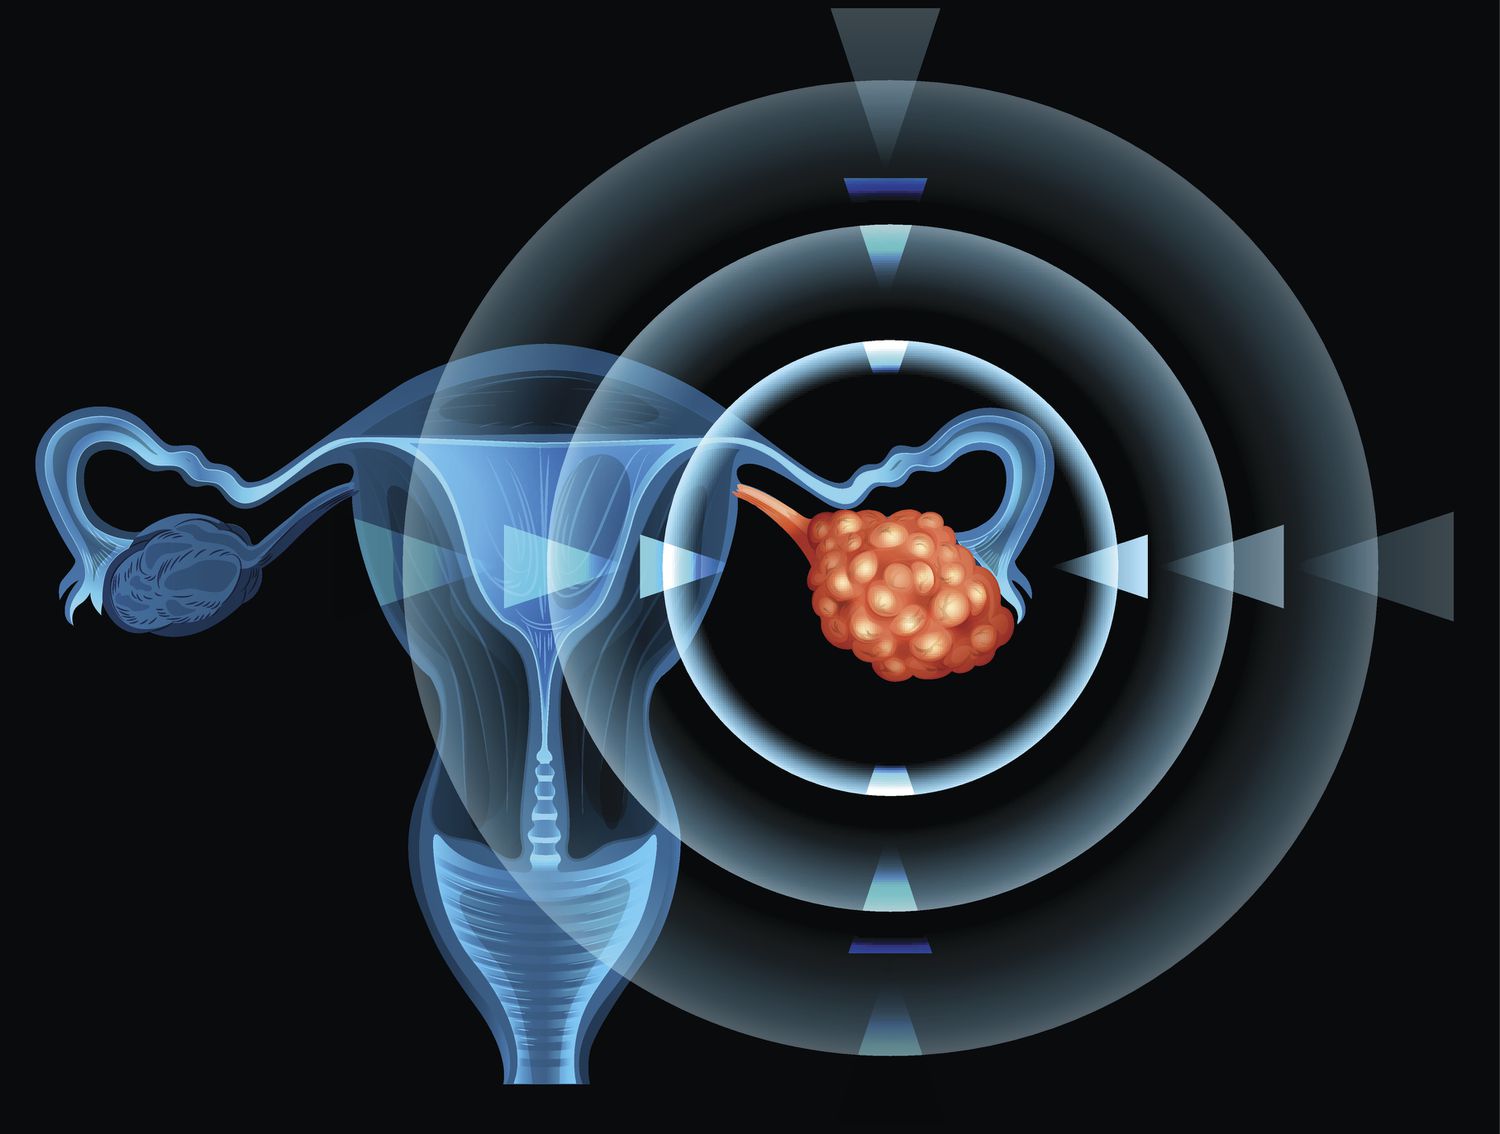

난소암 이란?

난소암은 자궁의 양쪽에 위치해 있어 난포 생산 및 여성 호르몬을 만드는 난소에 형성된 암을 뜻합니다. 대부분 발생하는 주 연령은 50대이며, 부인과 암의 약 20%를 차지하는 여성 암 사망률 1위인 무서운 질병입니다.